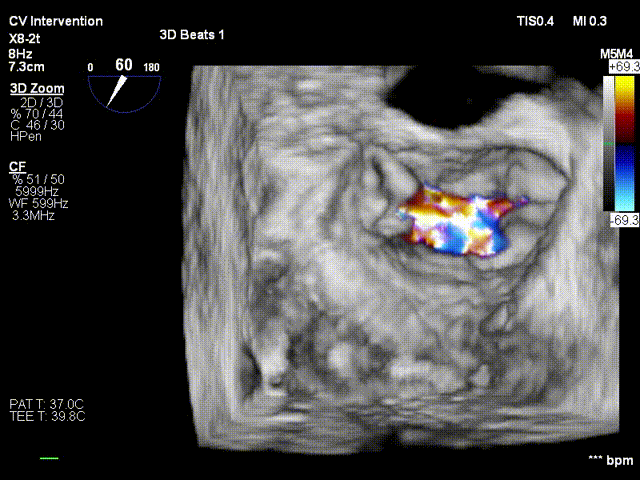

行TEE示:二尖瓣前叶A3脱垂合并重度反流(DMR4+),脱垂宽度11.6mm,脱垂高度5.8mm、二尖瓣口舒张期几何面积 6.00cm²、收缩期二尖瓣口偏心性反流束缩流颈宽度8.0mm、PISA定量瓣口EROA=0.61cm²。

患者平卧导管床,常规消毒铺巾,呼吸机辅助呼吸,穿刺右侧股静脉,于经食道超声指导下穿刺房间隔,造影确认穿刺针位于左房后。予super stiff置入左上肺静脉。于右股静脉沿super stiff推送MitraClip Guide Catheter于左房。于经食道超声指引下,推送XTR Clip Delivery System至二尖瓣左房面,食道超声确认12点钟方向推送至二尖瓣左室面,重新调整DC handle使Clip Arm至11点钟方向。顺利捕捉二尖瓣前叶A3及后叶P3区域,Grap down后夹闭Clip Arm。经食道超声评估二尖瓣返流由MR4+减少至微量,确认前叶有效夹持长度13mm,后叶有效夹持长度为11mm,确认瓣叶夹持牢固,释放瓣膜夹。经食道超声再次评估二尖瓣返流微量,二尖瓣压差1mmHg,退出MirtaClip系统,3DTEE评估房间隔 穿刺口少量左向右分流,未见右向左分流,未见心包积液,结束手术。